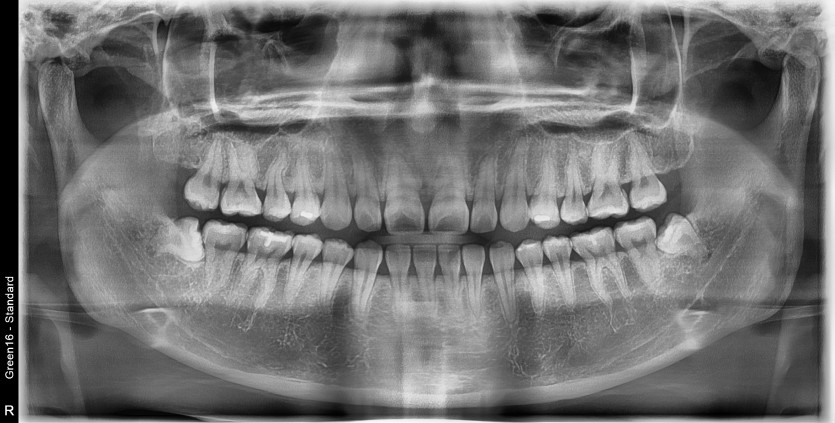

#38,48 사랑니 발치

구강 외과 전문의가 당일 발치했습니다.